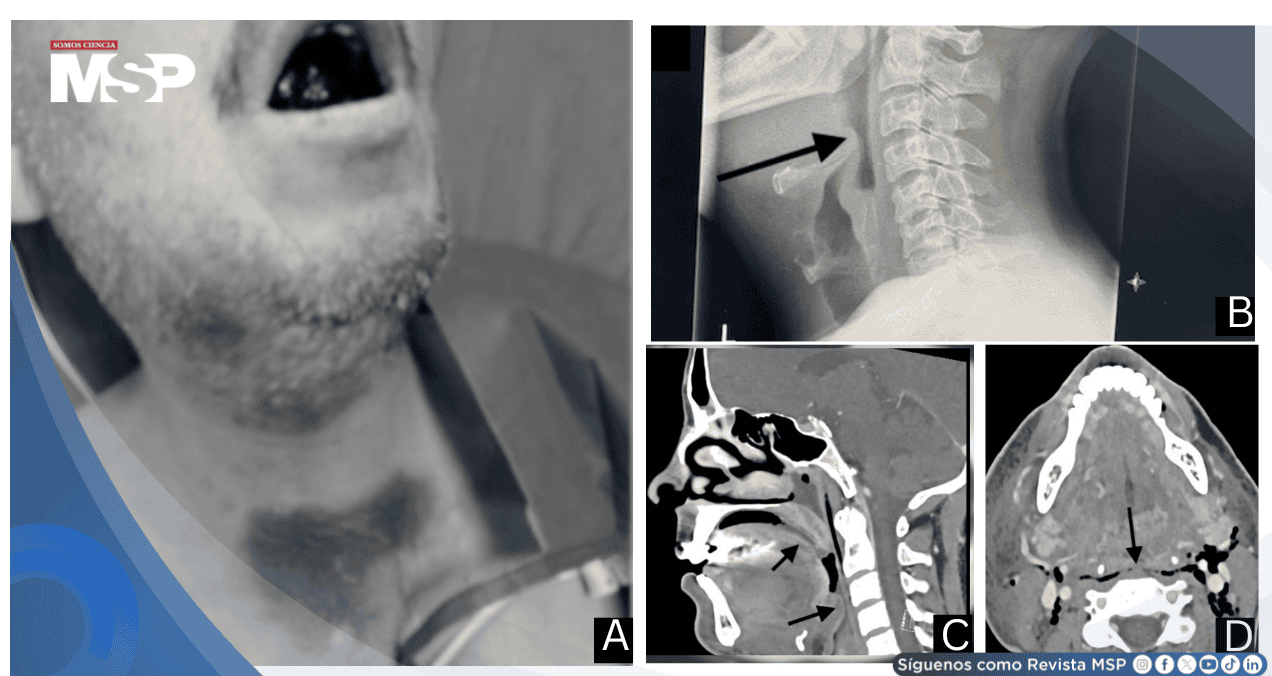

A su llegada, el paciente se encontraba incapaz de recostarse. El examen físico reveló múltiples equimosis en región supraesternal, cuello y áreas submandibulares, con edema y coloración violácea de la lengua.

La radiografía lateral de cuello demostró edema difuso del piso de la boca y área epiglótica con oclusión casi completa de la hipofaringe.

La tomografía computarizada de cuello realizada posteriormente confirmó edema extenso de tejidos blandos con compresión significativa de orofaringe e hipofaringe.